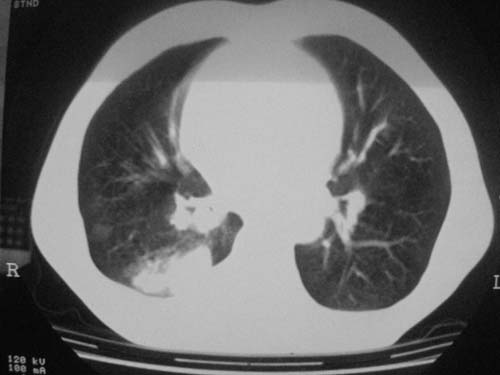

以下是引用科室第一人在2010-3-25 20:30:00的发言:[br]1:纵膈肿瘤性病变,恶性胸腺瘤可能性大伴纵膈右肺门淋巴结转移,右侧胸腔积液。[br]2:右侧肺门肿瘤性病变,纵膈淋巴结转移,右侧胸腔积液。右下叶转移。

以下是引用子期在2010-3-25 21:00:00的发言:[br]先考虑右中央型肺癌伴转移。

以下是引用江广1996在2010-3-25 22:49:00的发言:[br]通常肺癌向纵隔转移多见,纵隔肿瘤向肺内转移少见(有的表现为向肺内侵润)。本例以一元论考虑:右中心型肺癌并纵隔淋巴等多处转移。[br][br][本贴已被 江广1996 于 2010-3-25 22:50:07 修改过]

以下是引用yangyudong333在2010-3-26 6:43:00的发言:[br]“冰冻纵膈”,考虑纵膈淋巴瘤伴肺内及胸膜侵润。